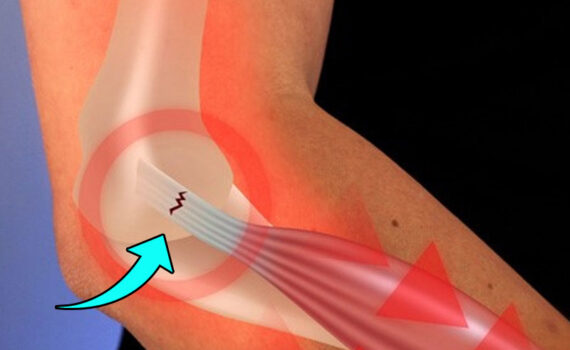

Antes de mais nada, procurar um especialista em cotovelo garante diagnóstico preciso e tratamento adequado para dores, lesões e limitações nessa articulação fundamental para os movimentos do braço. Dessa forma, o acompanhamento médico correto possibilita recuperação mais rápida e melhora significativa na qualidade de vida. Quando buscar um especialista em […]